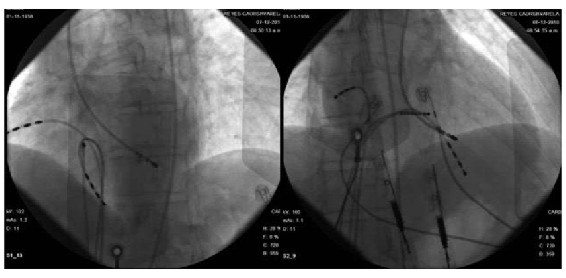

Se colocan catéteres cuadripolares en aurícula y ventrículo derechos y catéter octopolar deflectable en la región del His por acceso venoso femoral izquierdo. Intervalos básicos y conducción aurículoventricular (AV) normales. Con un extraestímulo ventricular (400/260) se induce en forma reproducible una taquicardia de QRS ancho de idéntica morfología a la taquicardia clínica (figura 2A) con disociación ventrículo atrial confirmando el diagnóstico clínico de taquicardia ventricular sostenida monomorfa (figura 3). Pobre tolerancia hemodinámica durante la arritmia con hipotensión sintomática. Se interrumpe con sobreestimulación ventricular (figura 4). No se inducen otras arritmias.

Concluido el estudio diagnóstico se coloca un introductor en la arteria femoral derecha a través del cual se avanza catéter de mapeo y ablación hasta el ventrículo izquierdo. Se mapea el ventrículo izquierdo en su sector septal y apical. A nivel de la unión del tercio basal y medio del septum posterior se define un sitio con registro en taquicardia de potencial de Purkinje 40 ms antes del QRS (figuras 5 y 6). Se realiza “pace mapping” (mapeo con estimulación desde ese sitio tratando de reproducir la morfología del QRS de la taquicardia clínica) (figura 2B), evidenciándose adecuada concordancia en la morfología del QRS en las 12 derivaciones. Se aplica radiofrecuencia en ese punto y en zona ligeramente más proximal. Luego de las 2 aplicaciones la arritmia no es más inducible, tampoco se inducen latidos aislados. No hubo complicaciones durante el procedimiento.

En el mapeo del sitio de origen durante la taquicardia pueden identificarse dos potenciales característicos en la región medioseptal: uno mesodiastólico y uno presistólico (potencial de Purkinje) (1,2,4,7,8).

Existen varios posibles sitios objetivo para la ablación de la arritmia propuestos por diferentes autores: el potencial mesodiastólico (1,2,7,8), el potencial de Purkinje (1-4,7,8), la zona de activación ventricular más precoz (2,4,8), el fascículo posterior de la rama izquierda (1,5) o el sitio de “pace mapping” perfecto (1-4,8). Durante la ablación puede objetivarse la prolongación gradual del intervalo entre los potenciales mesodiastólico y de Purkinje hasta producirse un bloqueo de la conducción entre ambos (1,7,8). La ablación es exitosa en 95% de los casos (1). En nuestro caso el sitio elegido y exitoso para la ablación fue aquel donde se evidenció el potencial de Purkinje y donde, además, el “pace mapping” demostró concordancia 12/12 (figura 2B).